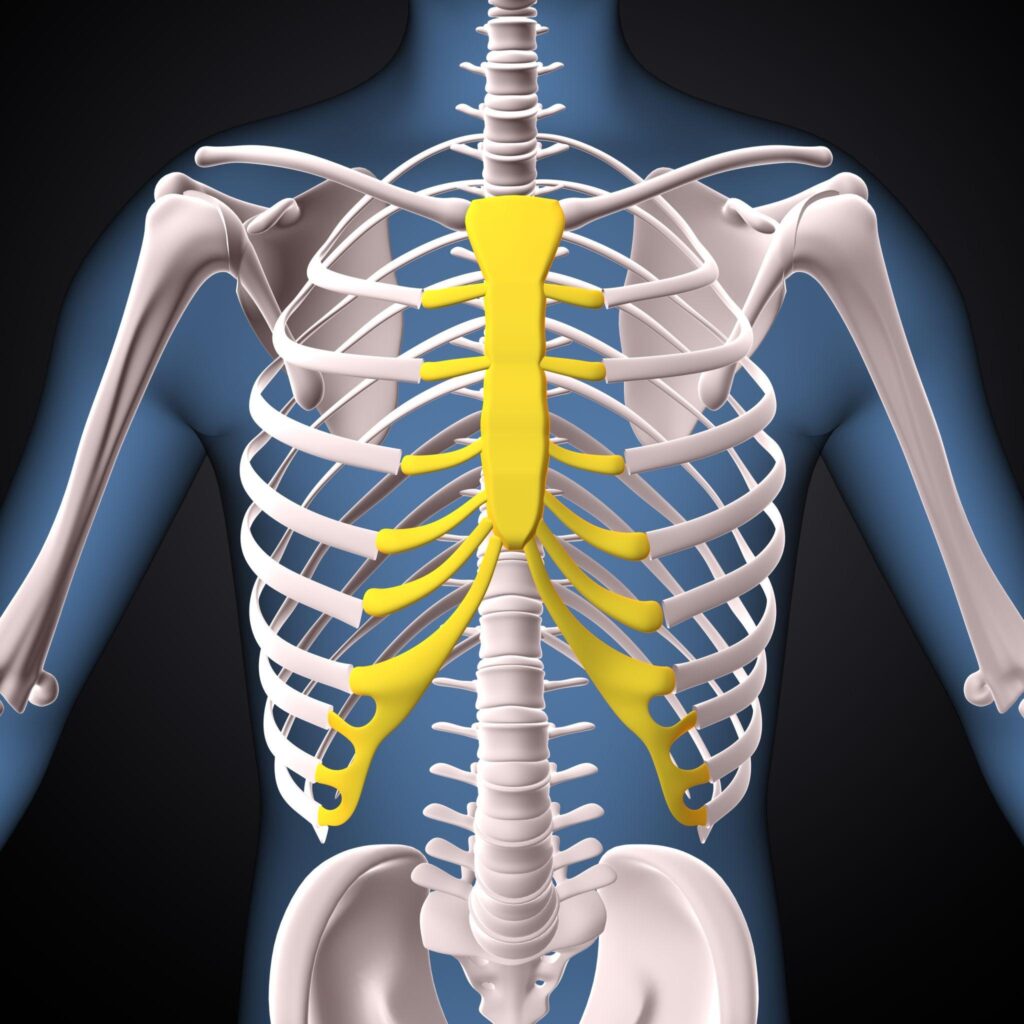

A cervical rib is an extra rib that arises from the seventh cervical vertebra in the neck. It is a congenital anatomical variation present at birth and occurs in a small percentage of the population.